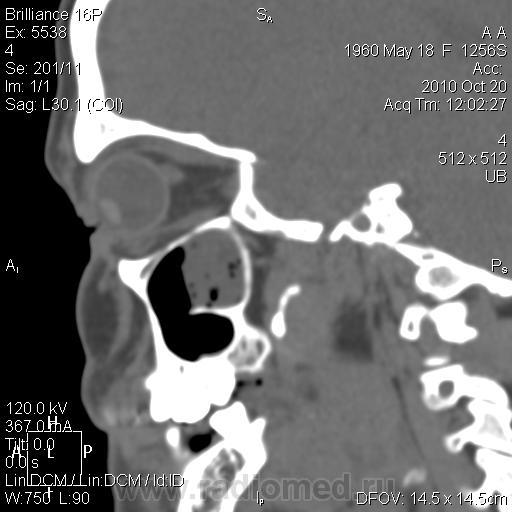

КТ. Нагноение кисты верхнечелюстной пазухи.

Женщина 30 лет, жалобы - головная боль, направлена для уточнения характера патологии ППН. Снимков пазух у меня нет.

Отграничено, ровный контур, гнойная (30 ед.Н) плотность

Да, надо признать, что уважаемая Людмила Григорьевна всегда старается объяснить, что не понятно коллегам. Но, я порассуждал с точки зрения «банальной эрудиции». Эта перегородка, в гайморовой полости, о чем свидетельствуют сканы, не полностью разделяет гайморову пазуху на две «изолированные полости», и сообщение между «разделениями» весьма не хилое есть, и если, предположить, что «то» сопли, то сопли, как всякая жидкая или полужидкая субстанция обязательно с учетом силы тяжести протекли вниз, чего не произошло, а, следовательно, процесс является, чем – то ограниченным, и имеющим определенную оболочку.

плотность. Есть серая шкала, от черного (воздух) до белого (кость). Остальное - оттенки серого. Я подобрала режим для демонстрации, чтоб наиболее выигрышно показать и пазуху, и ее содержимое. В данном случае больше вероятность за нагноение кисты: пузырьки газа, гнойная плотность патологического содержимого. Более жидкая субстанция растеклась бы, а полип имеет большую плотность (40-60 единиц). Было бы интересно проследить динамику, но пациентка категорически отказалась от пункции, так что вероятнее всего, что история на этом и закончится. А ППН можно и на животе делать с запрокидыванием головы назад - только для пациента не очень удобно, а при шейном остеохондрозе иногда и невозможно.